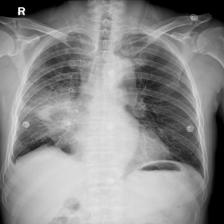

To pre-train a high-performance X-ray foundation model, the first thing we need to do is the collection of large-scale X-ray images. Therefore, a large-scale and high-resolution dataset that contains X-ray medical images is collected for the pre-training. Some representative samples are visualized in Fig. 3.